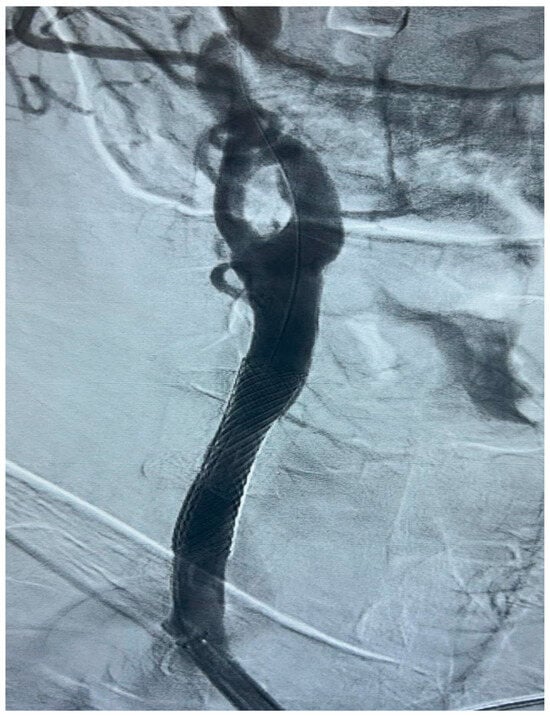

Figure 3. Selective DSA (Digital Subtraction Angiography) of right CCA showing significative (>50%) stenosis of right ICA, in post-ostial tract.

The procedure is performed in the angiographic suite, under mild sedation to monitor the neurological status of the patient, by arterial vascular access, usually femoral. With the wire–catheter system, the common carotid artery (CCA) of the pathological side is selectively catheterized and a diagnostic angiography is performed to identify the stenosed area (Figure 3). The stenosis carotid tract is crossed through the wire–catheter system, and only after the placement of a neuroprotection device in the ICA, a balloon angioplasty is performed to compress the atheromatic lesion and restore the original luminal vessel diameter. Regarding neuroprotection, today we have two classes of embolic protection devices available: a coaxial umbrella-like filter positioned in the distal ICA (Figure 4) or hemodynamic balloon block systems with reversal flow that can be placed either proximally or distally to the carotid stenosis with overlapping results in reducing the distal embolic phenomena risk but with a higher rate of periprocedural vasospasm in the case of a distal umbrella-like filter [53]. At this point, it is necessary to inject 1 mg of atropine to avoid vasospasm before releasing a permanent endovascular stent. We have three types of endovascular stents such as open-cell, closed-cell, or double-layer (Figure 5). Open-cell stents were worse than closed-cell due to the higher degree of plaque protrusion and the procoagulant state induced by the stent that can trigger embolic phenomena, recording a higher rate of stroke or restenosis at 30 days. The double-layer stents are still in the process of approval by the FDA although they have shown in some clinical trials strongly encouraging results with a risk of adverse events at 30 days <2% [54].